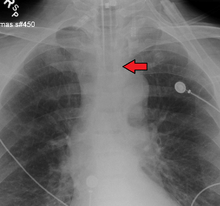

Ideally, at least one of the methods utilized for confirming tracheal tube placement will be a measuring instrument. Waveform capnography has emerged as the gold standard for the confirmation of tube placement within the trachea. Other methods relying on instruments include the use of a colorimetric end-tidal carbon dioxide detector, a self-inflating esophageal bulb, or an esophageal detection device.[33] The distal tip of a properly positioned tracheal tube will be located in the mid-trachea, roughly 2 cm (1 in) above the bifurcation of the carina; this can be confirmed by chest x-ray. If it is inserted too far into the trachea (beyond the carina), the tip of the tracheal tube is likely to be within the right main bronchus — a situation often referred to as a "right mainstem intubation". In this situation, the left lung may be unable to participate in ventilation, which can lead to decreased oxygen content due to ventilation/perfusion mismatch.[34]